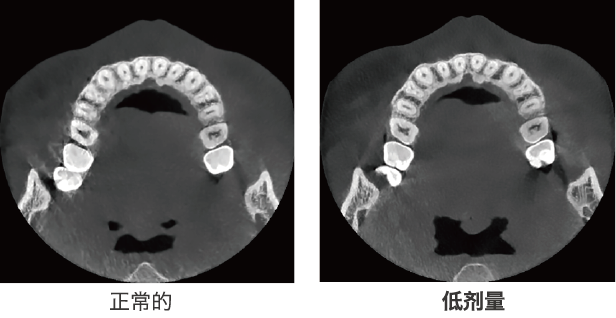

低劑量,高質量

通過先進的工程學技術,低劑量的X射線也可以獲得高質量的圖像。

降噪技術:bright CT無噪點圖像,不會丟失有價值的細節,并允許低劑量模式通過降低噪點來獲得影像。此功能在使用小體素模式(例如在牙髓成像模式下)。